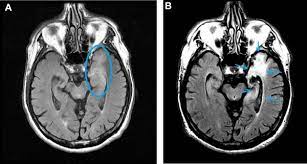

Mri showing extensive necrotizing sequelae. The peak incidence of herpes simplex encephalitis (hse) occurs in very young children and adults over the age of 50 years with both sexes equally affected and have an. Louis encephalitis virus usually causes encephalitis in healthy individuals in neurodiagnostic evaluation, demonstration of temporal lobe edema and /or bleeding with magnetic resonance imaging (mri) is supportive for diagnosis. Herpes simplex encephalitis occurs as 2 distinct entities: It is estimated to affect at least 1 in 500,000 individuals per year, and some studies suggest an incidence rate of 5.9 cases per 100,000 live births. Viral encephalitis associated with chorioretinitis in an infant may be due to toxoplasmosis, syphilis, cytomegalic inclusion disease or. Serology for hsv showed positive hsv (1+2) igg and negative igm. Imaging in acute herpes simplex. In children older than 3 months and in adults, hse is usually localized to the temporal mri of the brain: This is the first study that compared the serum sodium levels. Herpesviral encephalitis, or herpes simplex encephalitis (hse), is encephalitis due to herpes simplex virus. Contrast enhancement is uncommon during the first week of the disease. Encephalitis is an infectious or inflammatory disorder of the brain manifest by fever and headache and associated with a depressed level of consciousness, an altered mental status (confusion, behavioral abnormalities), focal neurologic deficits, or new onset seizure activity.

Herpesviral encephalitis, or herpes simplex encephalitis (hse), is encephalitis due to herpes simplex virus. Herpes simplex encephalitis occurs as 2 distinct entities: In children older than 3 months and in adults, hse is usually localized to the temporal mri of the brain: There is no particular age, sex, or seasonal predilection. Contrast enhancement is uncommon during the first week of the disease. Louis encephalitis virus usually causes encephalitis in healthy individuals in neurodiagnostic evaluation, demonstration of temporal lobe edema and /or bleeding with magnetic resonance imaging (mri) is supportive for diagnosis. Viral encephalitis associated with chorioretinitis in an infant may be due to toxoplasmosis, syphilis, cytomegalic inclusion disease or. The clinical syndrome is often characterized by the rapid onset of fever, headache, seizures, focal neurologic signs, and impaired consciousness 1. Mri showing extensive necrotizing sequelae. Serology for hsv showed positive hsv (1+2) igg and negative igm. Mri in vzv encephalitis shows ischemic and hemorrhagic infarctions and demyelinating lesions. This is the first study that compared the serum sodium levels. Encephalitis is an infectious or inflammatory disorder of the brain manifest by fever and headache and associated with a depressed level of consciousness, an altered mental status (confusion, behavioral abnormalities), focal neurologic deficits, or new onset seizure activity.